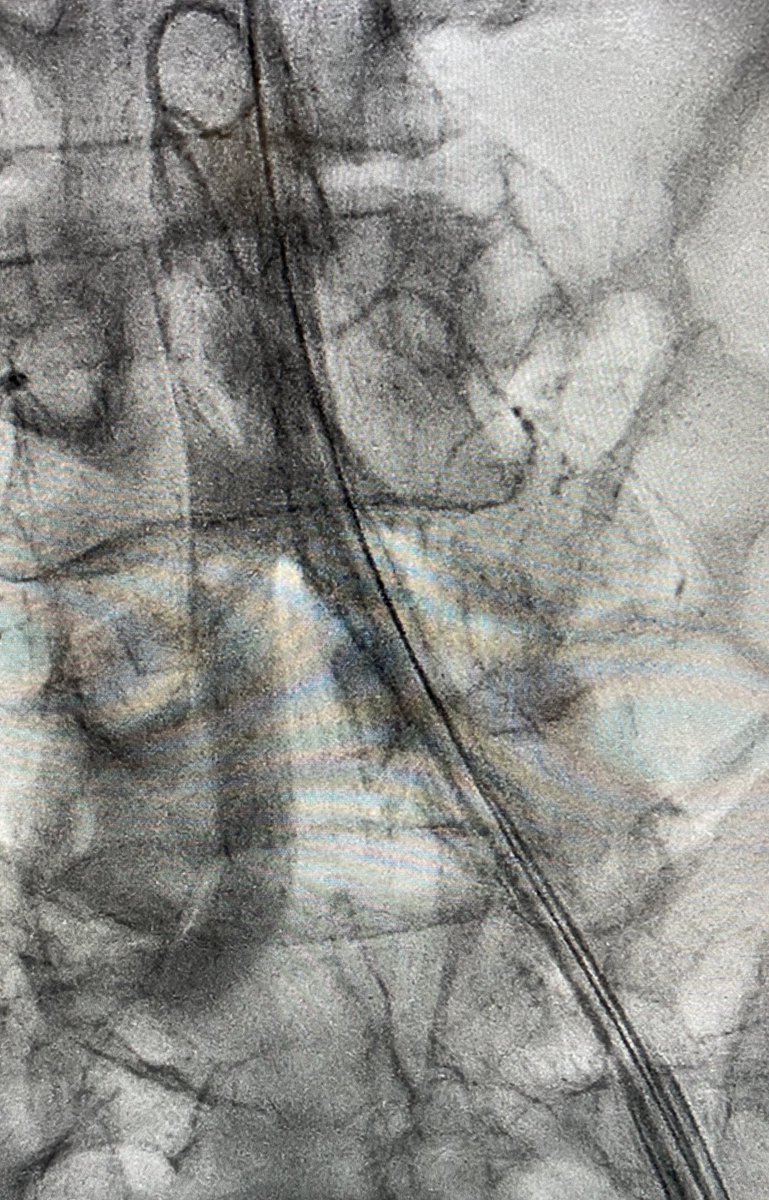

1/7 Vascular Access for Shock-MCS. Do it the same way every time (“slow is smooth, smooth is fast”). Fluoro Femoral Head. US-guided Micropuncture access, observe micro wire advancement, perform access site angiogram (with wire left in), Preclose (single Perclose)...

2/7 Aorto-Iliac angiography (with run-off) for complete pre-insertion vascular assessment...

3/7 Impella observed going in. Take a moment to remove slack, achieve stable device position. Always place Swan with Impella in Shock...